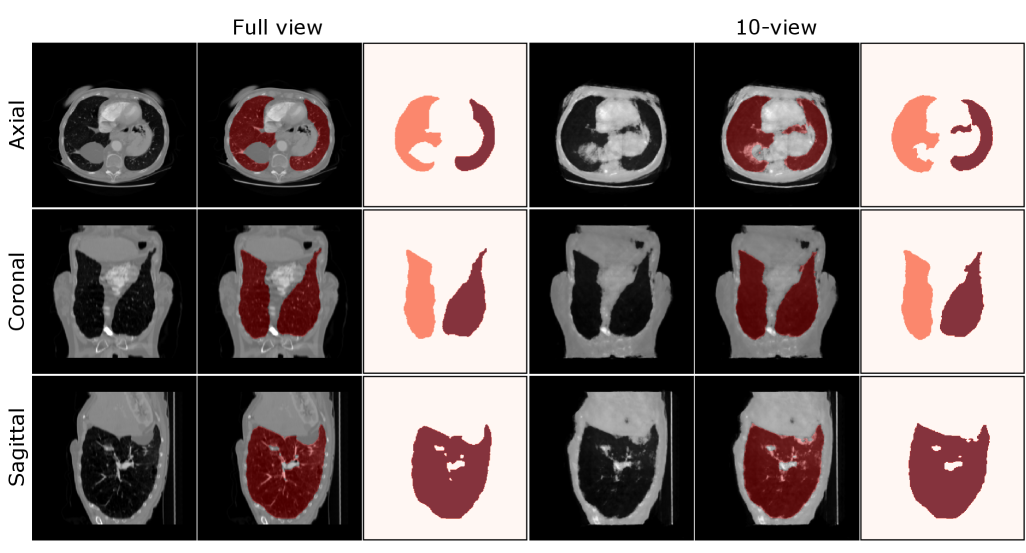

Refer to caption

Figure 4: Visualization of 10-view reconstructed chest CT (from top to bottom: axial, coronal, and sagittal slice). This figure highlights the key advantage of our method in preserving fine details. While DIF-Net and DIF-Gaussian successfully recover the general anatomy, they produce overly smoothed images that lose high-frequency information, as evidenced by the blurry details in the zoomed-in views. In contrast, our method yields visibly sharper reconstructions across the axial, coronal, and sagittal planes, achieving a fidelity much closer to the ground-truth image.

5.3 Qualitative Analysis

We present visual comparisons to further demonstrate the differences between our model and baseline methods. We focus on 6-view reconstructions as this represents the most challenging sparse-view scenario and best showcases reconstruction quality differences (Figures 4 and 5). Traditional methods such as FDK(Feldkamp et al., 1984) and SART (Andersen and Kak, 1984) exhibit noticeable artifacts and fail to preserve fine anatomical structures, while DIF-Net (Lin et al., 2023) and DIF-Gaussian (Lin et al., 2024a) show improvements but still struggle to capture critical high-frequency details and tissue boundaries. Our model produces reconstructions with enhanced clarity and accurate contrast representation, effectively preserving high-frequency features while minimizing artifacts. On the ToothFairy dataset, similar patterns emerge: traditional methods fail to recover fine dental structures. Our approach demonstrates improved capability in reconstructing sharp boundaries and complex anatomical features while maintaining high fidelity under sparse projection conditions across different medical imaging domains.